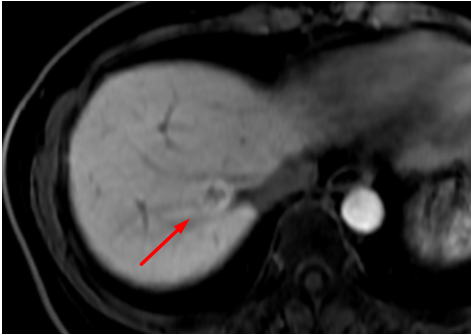

Hình ảnh tổn thương gan không rõ bản chất khi chụp MRI thường

Hình ảnh tổn thương gan giữ thuốc đối quang từ đặc hiệu tế bào gan thì gan mật, gợi ý tính chất của tăng sản thể nốt khu trú (FNH)